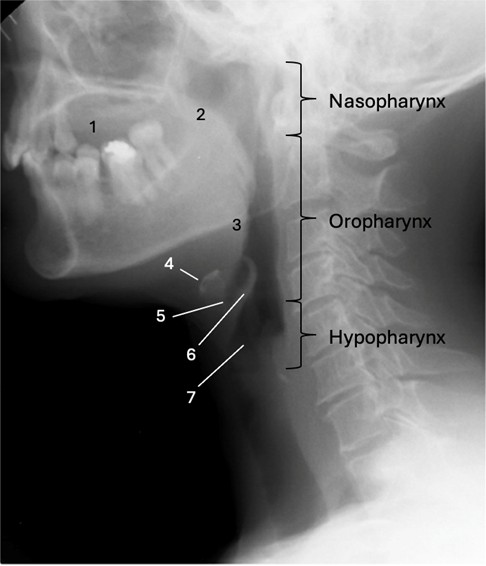

The radiographic anatomical landmarks are labelled on the lateral view in Figure 1.

Figure 1: Radiographic anatomical landmarks on lateral view.1 - oral cavity; 2 - soft palate; 3 - base of the tongue; 4 - hyoid bone; 5 - vallecula; 6 - epiglottis; 7 - laryngeal vestibule